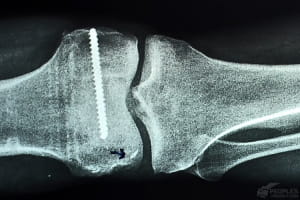

Після травми коліно чоловіка практично не функціонує: порвані зв'язки

"Коліно чоловіка практично не функціонує: кістки, які мусять рухатися точно відповідно одна до одної, безпорадно бовтаються з боку в бік. Це призводить до сильного болю під час ходи та будь-яких навантажень, адже коліно свою роботу не робить. Більше того, це загрожує подальшими серйозними ускладненнями, лікувати які буде і тяжче, і набагато дорожче... Щоб пошвидше здихатися, у держлікарнях закрили очі на всі проблеми і "намалювали" невідомо що замість діагнозу", – розповідає Володимир.

Тому за бійця взялися ми з вами та лікарі благодійного проекту "Біотех-реабілітація поранених". Володимиру вже зробили першу операцію.